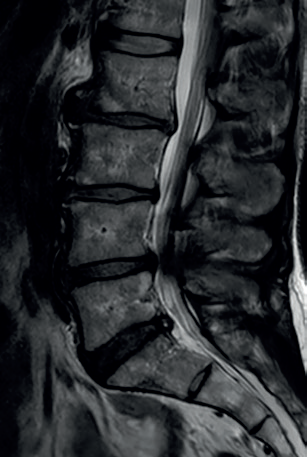

• Magnetická rezonance (MRI)

• Dominantní metoda v zobrazení měkkotkáňových postižení – zejména degenerativních změn včetně herniací meziobratlových plotének, dále metastatických postižení nebo spondylodiscitidy (zejména T2 STIR sekvence).

Obr. 4 Multietážová lumbální spinální stenóza s maximálním nálezem v etáži L4/5 s protruzí intervertebrálního disku a spondylartrózou zadních segmentůNejčastější oblastí zájmu chirurgické terapie jsou degenerativní změny v oblasti dolní bederní páteře typicky podmiňující rozvoj syndromu lumbální spinální stenózy. Příčinou je většinou protruze/herniace intervertebrálního disku, dále např. těžká spondylartóza, případně jejich kombinace (obr. 4). V případech foraminálních herniací nereagujících na CT periradikulární obstřik je volena metoda mikrodekomprese (miniinvazivně za použití mikroskopu/endoskopu), která je případně doplněna sekvestrektomií (odstranění dislokované části vyhřezlého disku). Pokud se jedná o širokou centrální protruzi, která mohutně utlačuje durální vak, pak je často nutná již široká dekomprese formou hemi‑/laminektomie, dále odstranění poškozeného disku (diskektomie) s náhradou vytvořeného prostoru. Součástí výkonu je typicky také stabilizace intervenovaných segmentů transpedikulárními šrouby – tedy vytvoření pevné vnitřní fixace. Náhrada prostoru disku je prováděna buď umělými (kombinace karbonu a polyetheretherketonu; syntetické náhrady kosti) nebo biologickými (autograft/alograft) implantáty s cílem dosažení pevného meziobratlového srůstu (tzv. intersomatické fúze).